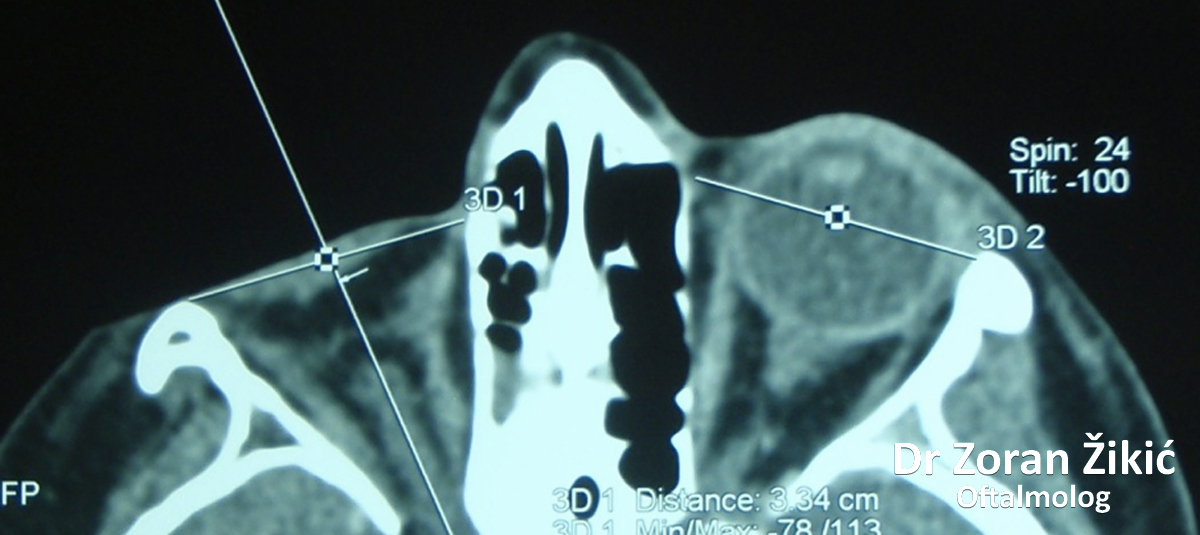

3D rekonstrukcija koštanih struktura lica, pomoću

CT (kompjuterizovana tomografija) visoke rezolucije